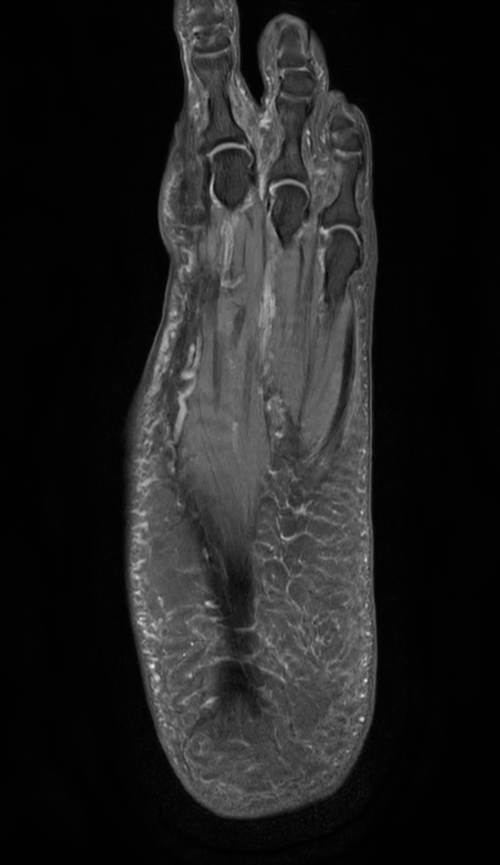

Ankle/Foot imaging post-amputation

Patient with partial amputation of the foot

3D VIEW PDw SPAIR - Coronal reformat

-

3D VIEW PDw SPAIR - Axial reformat